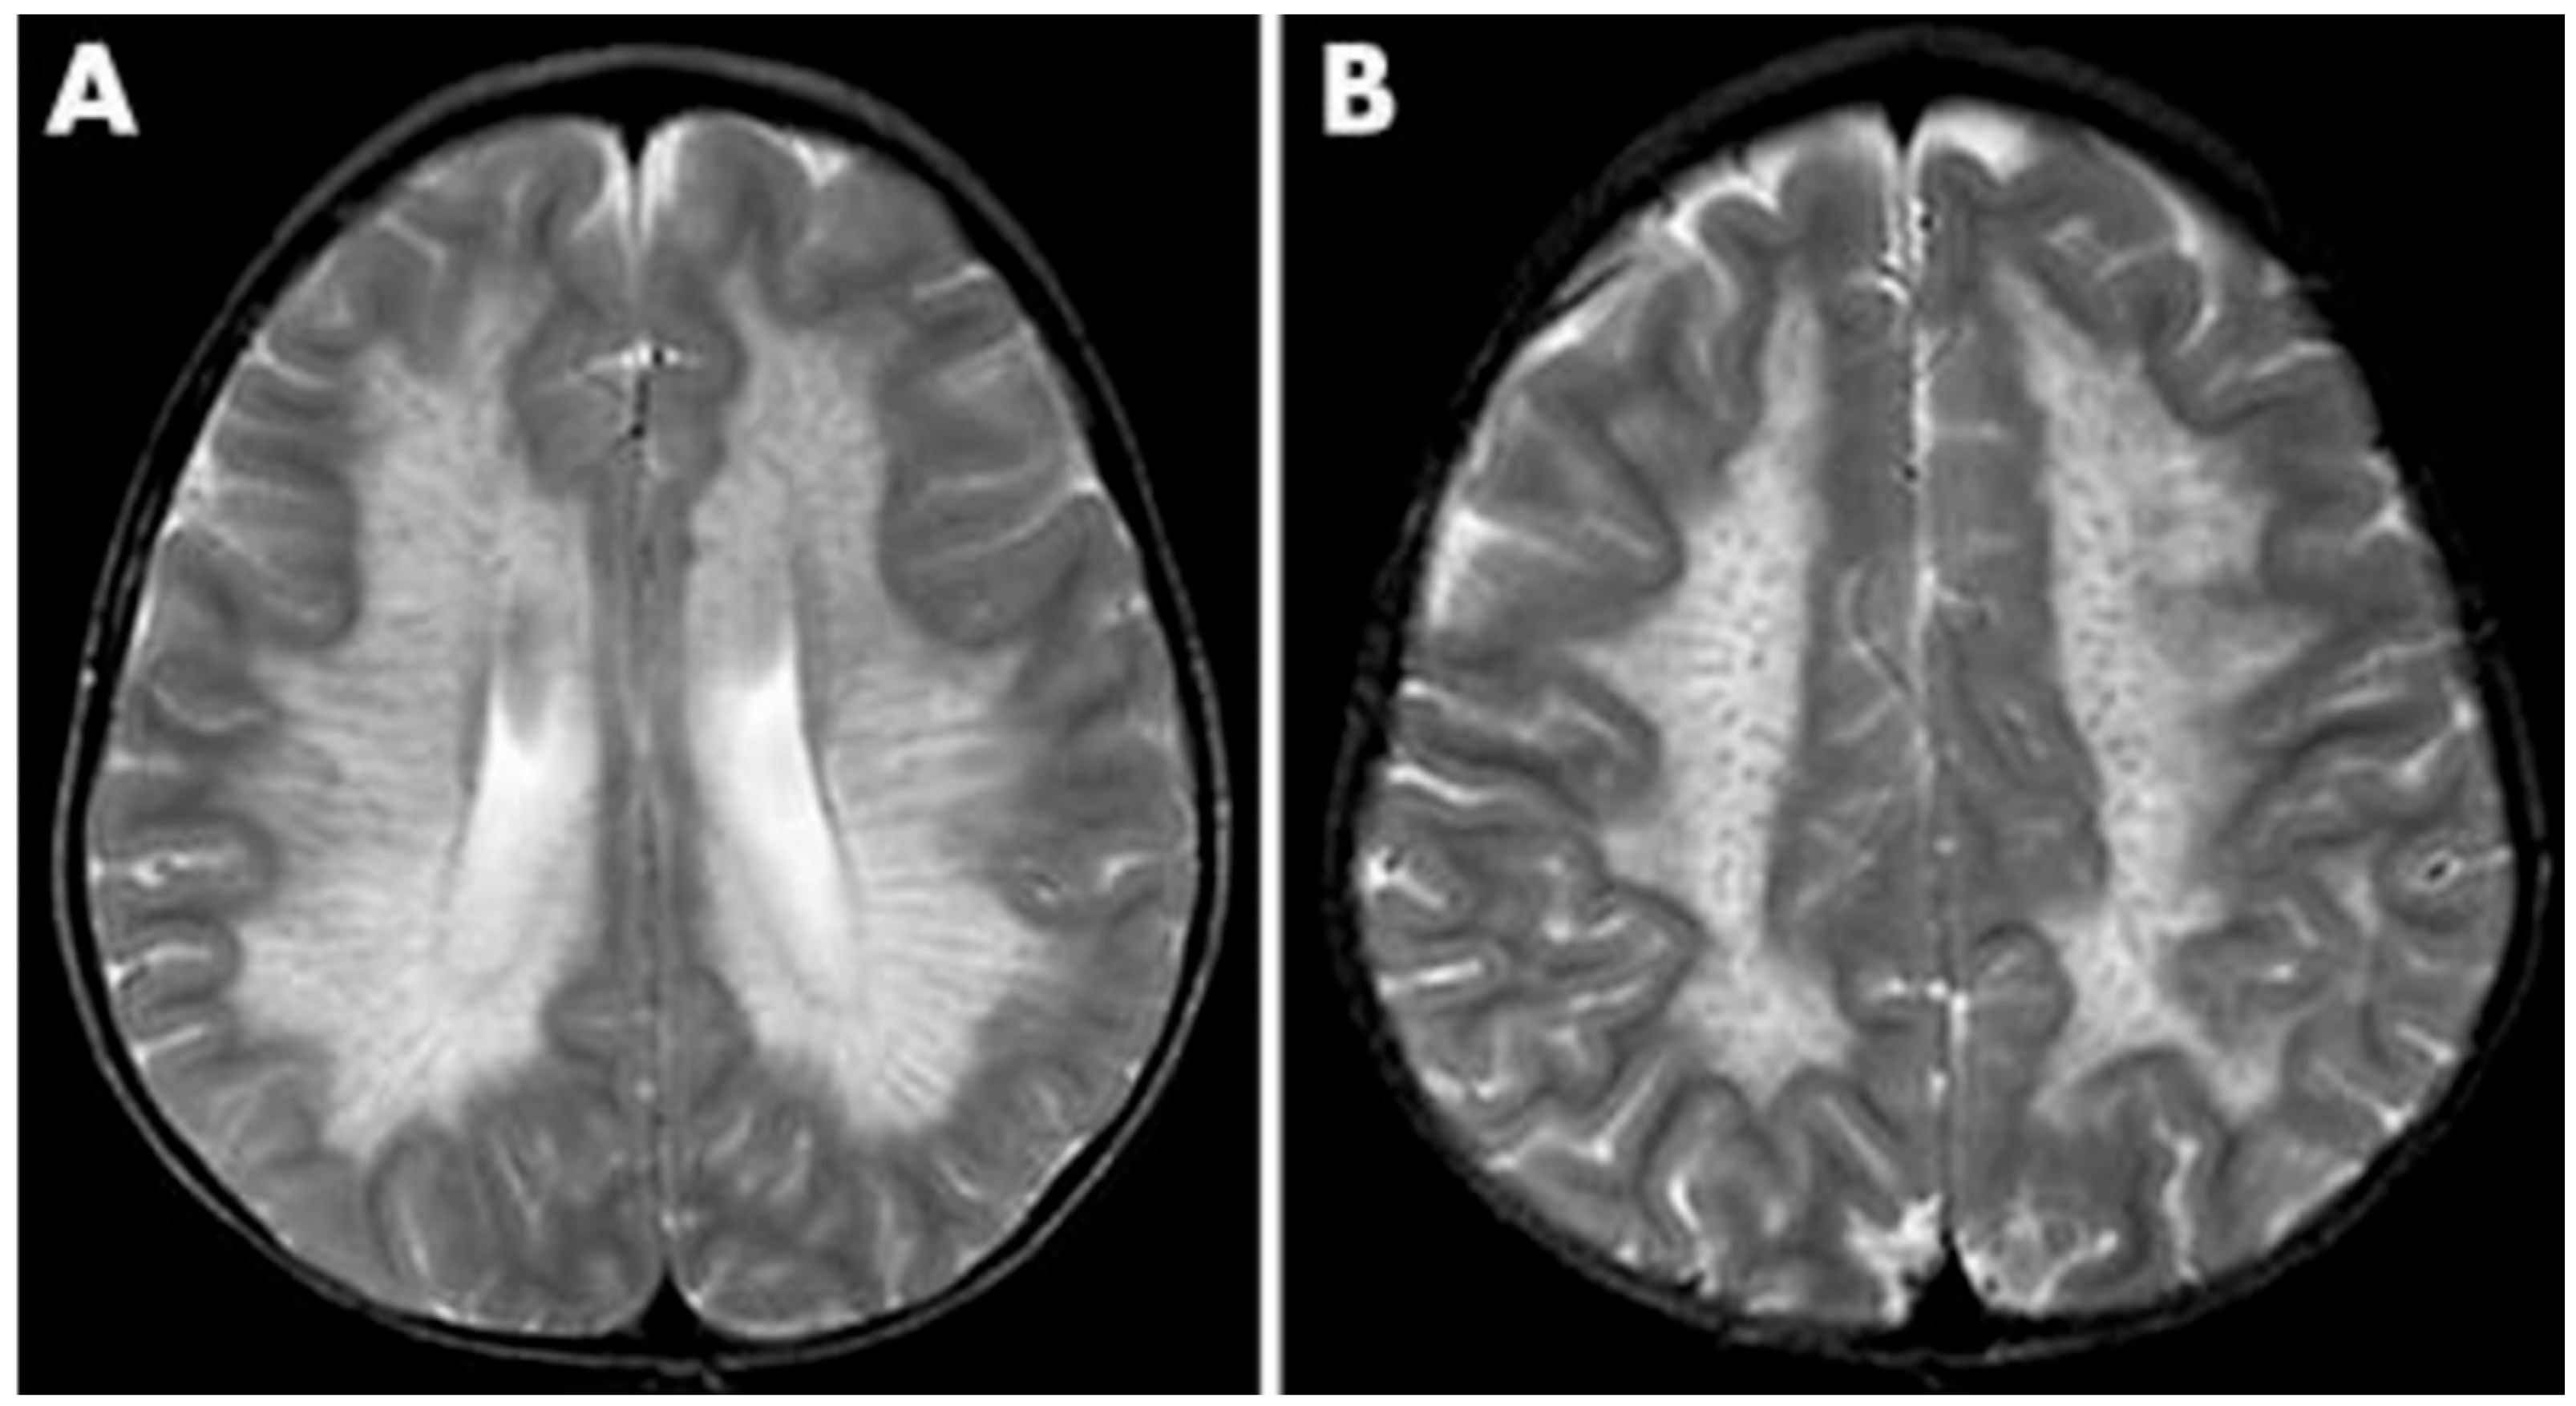

2.5. Alexander Disease